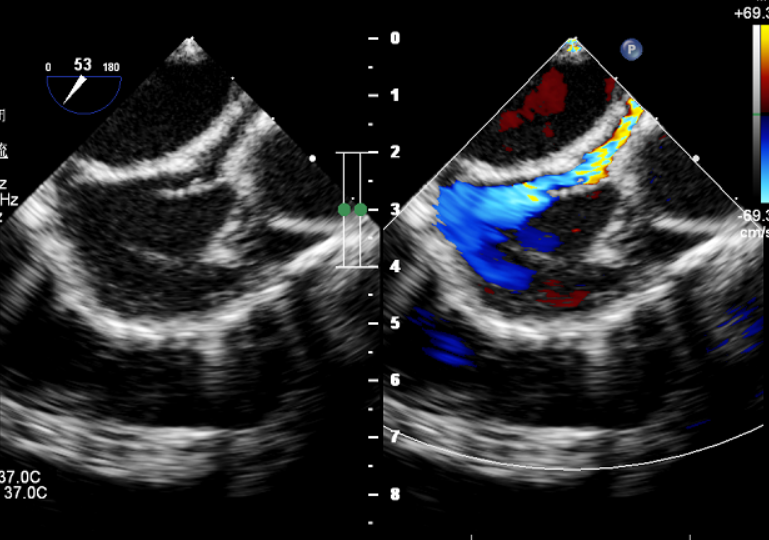

术前超声检查

超声下可见左冠状动脉异常增宽 右心房后壁侧可见高速紊乱的血流信号

左回旋支向右发出一支血管前走行汇入右心房